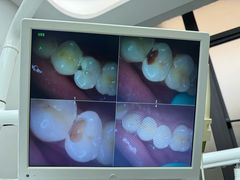

• 牙博士口腔品牌连锁(杨浦店)

• -牙博士口腔品牌连锁(杨浦店)

maomao786768 | 25-05-05